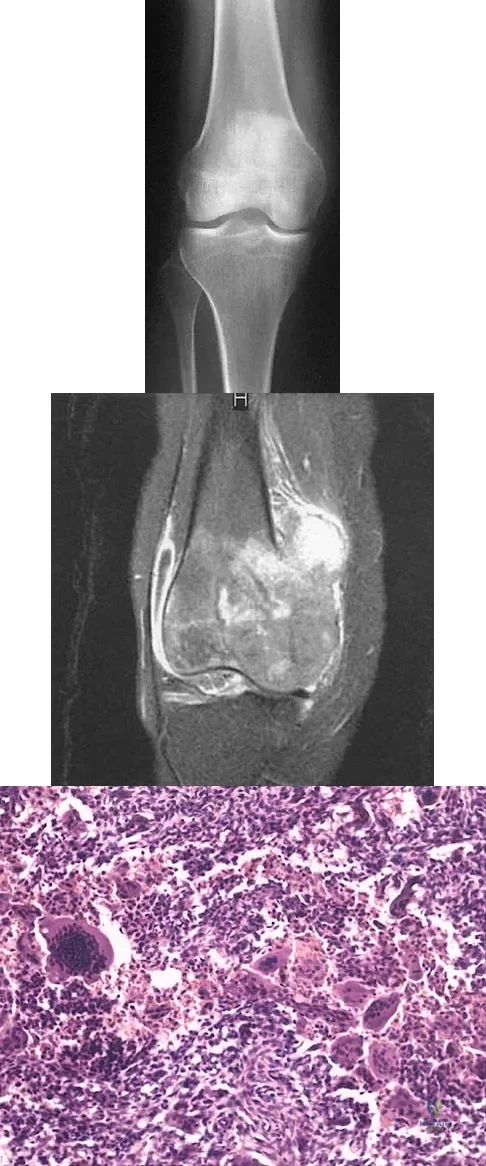

A 21-year-old man has had progressive right knee pain for the past 2 months that is exacerbated with weight-bearing activities. A plain radiograph and an MRI scan are shown in Figures 43a and 43b. A biopsy specimen is shown in Figure 43c. According to the Enneking staging system of tumor classification, the lesion should be classified as what stage?

Explanation